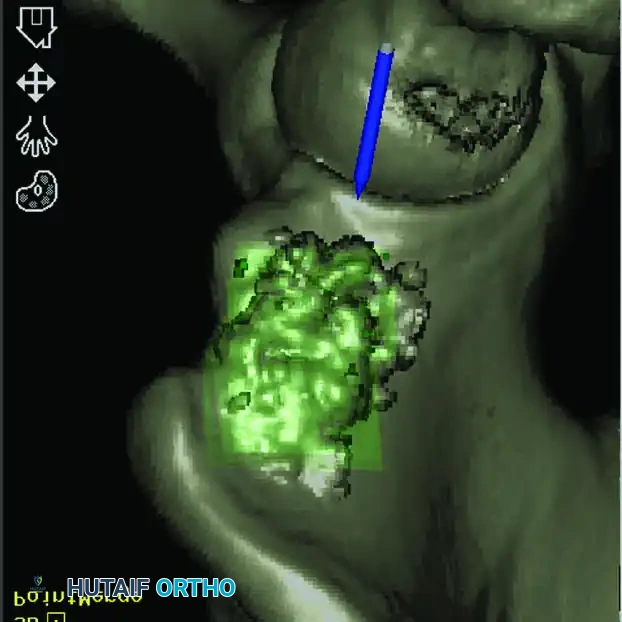

Intraoperative Imaging and Margin Assessment

Continuous intraoperative assessment using fluoroscopy and frozen section pathology is mandatory. The following images demonstrate various stages of complex upper extremity resections, allograft preparations, and prosthetic implantations across the humerus and elbow joint.